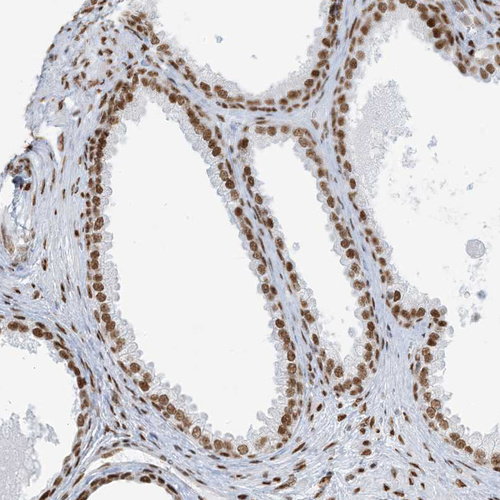

Immunohistochemical staining of human endometrium shows strong nuclear positivity in glandular cells.